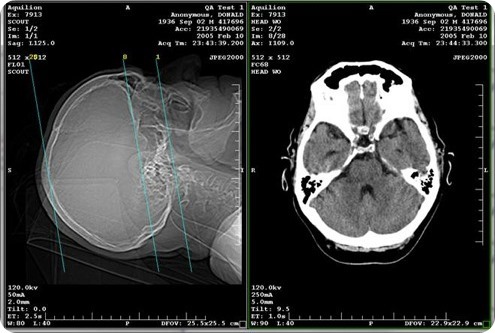

The most common method of image sharing over the past decade has been compact discs (CDs). Physicians place exams and reports on CDs and give them to patients to take to their medical appointments for treatment or second opinions; however approximately 20 percent of these CDs contain corrupt or bad files.

When a CD is unreadable or lost, a patient is usually re-scanned, which exposes the individual to added radiation and delays treatment. In fact, there are more than 600 million exams done each year in the U.S. and 10 to 20 percent of those are duplicate exams - totaling $10 billion in excess.

Medical image sharing helps streamline transfer and referral processes, eliminate duplicate testing and improve patient outcomes and care coordination.